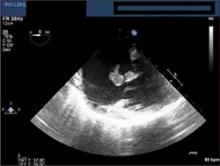

Our patient was admitted to the telemetry unit, given aggressive IV hydration, and started empirically on vancomycin secondary to the risk for infectious endocarditis (IE). On hospital Day 1, the patient’s blood cultures returned positive for methicillin-sensitive Staphylococcus aureus and an echocardiogram revealed a large tricuspid vegetation (FIGURE 1).

FIGURE 1

Echocardiogram reveals tricuspid vegetation